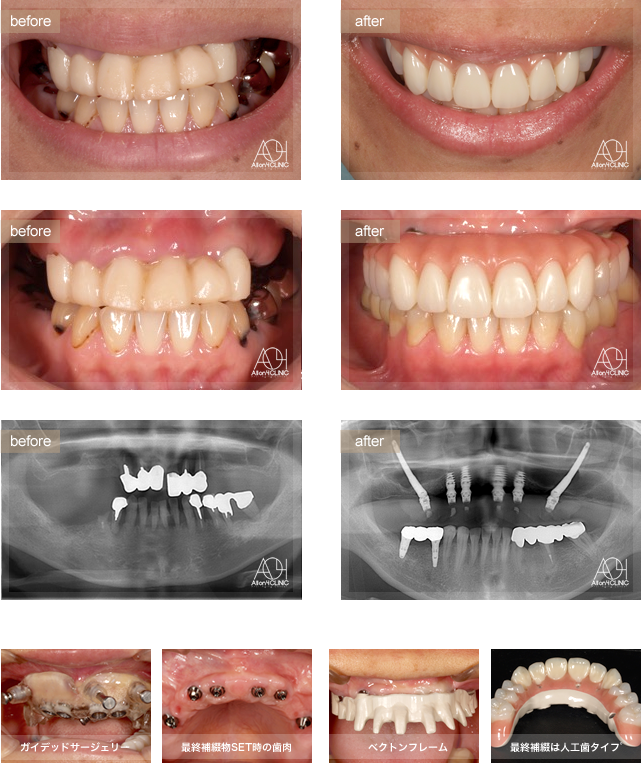

- Maxilla Zygoma Hybrid

- Under All-on-4

- Maxilla All-on-4

上顎両側Zygoma、前方4本のNobel Activeインプラントを使用。

上顎上部構造はペクトンフレーム(歯肉:アクリリックレジン 歯:人工歯)を採用。